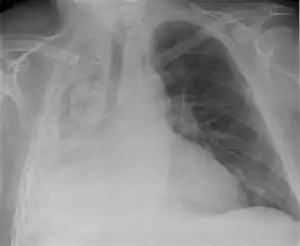

| Left tension pneumothorax with a large, well-demarcated area devoid of lung markings with tracheal deviation and movement of the heart away from the affected side. |

Tension pneumothorax

Tension pneumothorax is an emergent condition in which air gets trapped in the space between the chest wall and the lung. This space is referred to as the pleural space. Because air can't escape from this space, the pocket of air grows larger and larger which results in collapse of the lung closest to the pneumothorax. Forces are transmitted to the mediastinum and effectively "push" the mediastinal structures to the opposite side of the chest. [5]